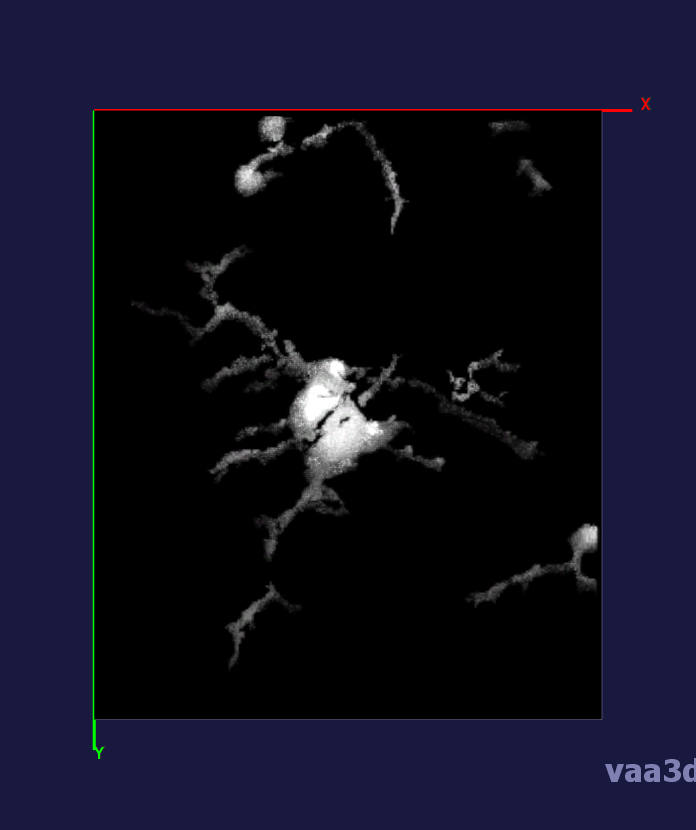

In our experiments, we compare the coupled TuFF-BFF microglia segmentation results with those given by L2S [21] and the Chan-Vese segmentation method [22]. The groundtruth in 3D was attained by manually tracing the object slice by slice from the z-stack. It must be noted that this was done by eye and could have some error. Figure 2 shows the visual comparison of the segmentation results for our dataset. Our result shown on the third column captures both the soma and processes. Figure 3 shows the Dice coefficient comparison of each segmentation method to the ground truth. Since the soma is much larger than the fine processes in the microglia, the processes have less volumetric impact on the similarity score. As explained in Section 1, segmenting the processes is important for quantifying the extension from the soma and its volume of surveillance. We use the Dice coefficient to quantitatively compare the ramification by taking the convex hull of the resulting segmentation. The Dice coefficient is a similarity measure that is computed using with where is the ground truth and is the compared image.

From Figure 4, the average Dice score for coupled TuFF-BFF was 0.77, compared to 0.53 for L2S [21] and .58 for Chan-Vese [22]. It must be noted that L2S required manual user initialization for each 2D image in the stack. While the Chan-Vese method has automatic seed selection, our coupled TuFF/BFF method was the only method that was a true 3D segmentation algorithm. L2S could not consistently capture the entire processes due to the intensity inhomogeneity throughout the object and background noise. The Chan-Vese segmentation could capture the extensions of the processes but did not work well with noise and attained false positives in the reconstruction. Since our method uses the tubular and blob information of the object to separate foreground and background, the segmentation only evolved within the object boundaries.